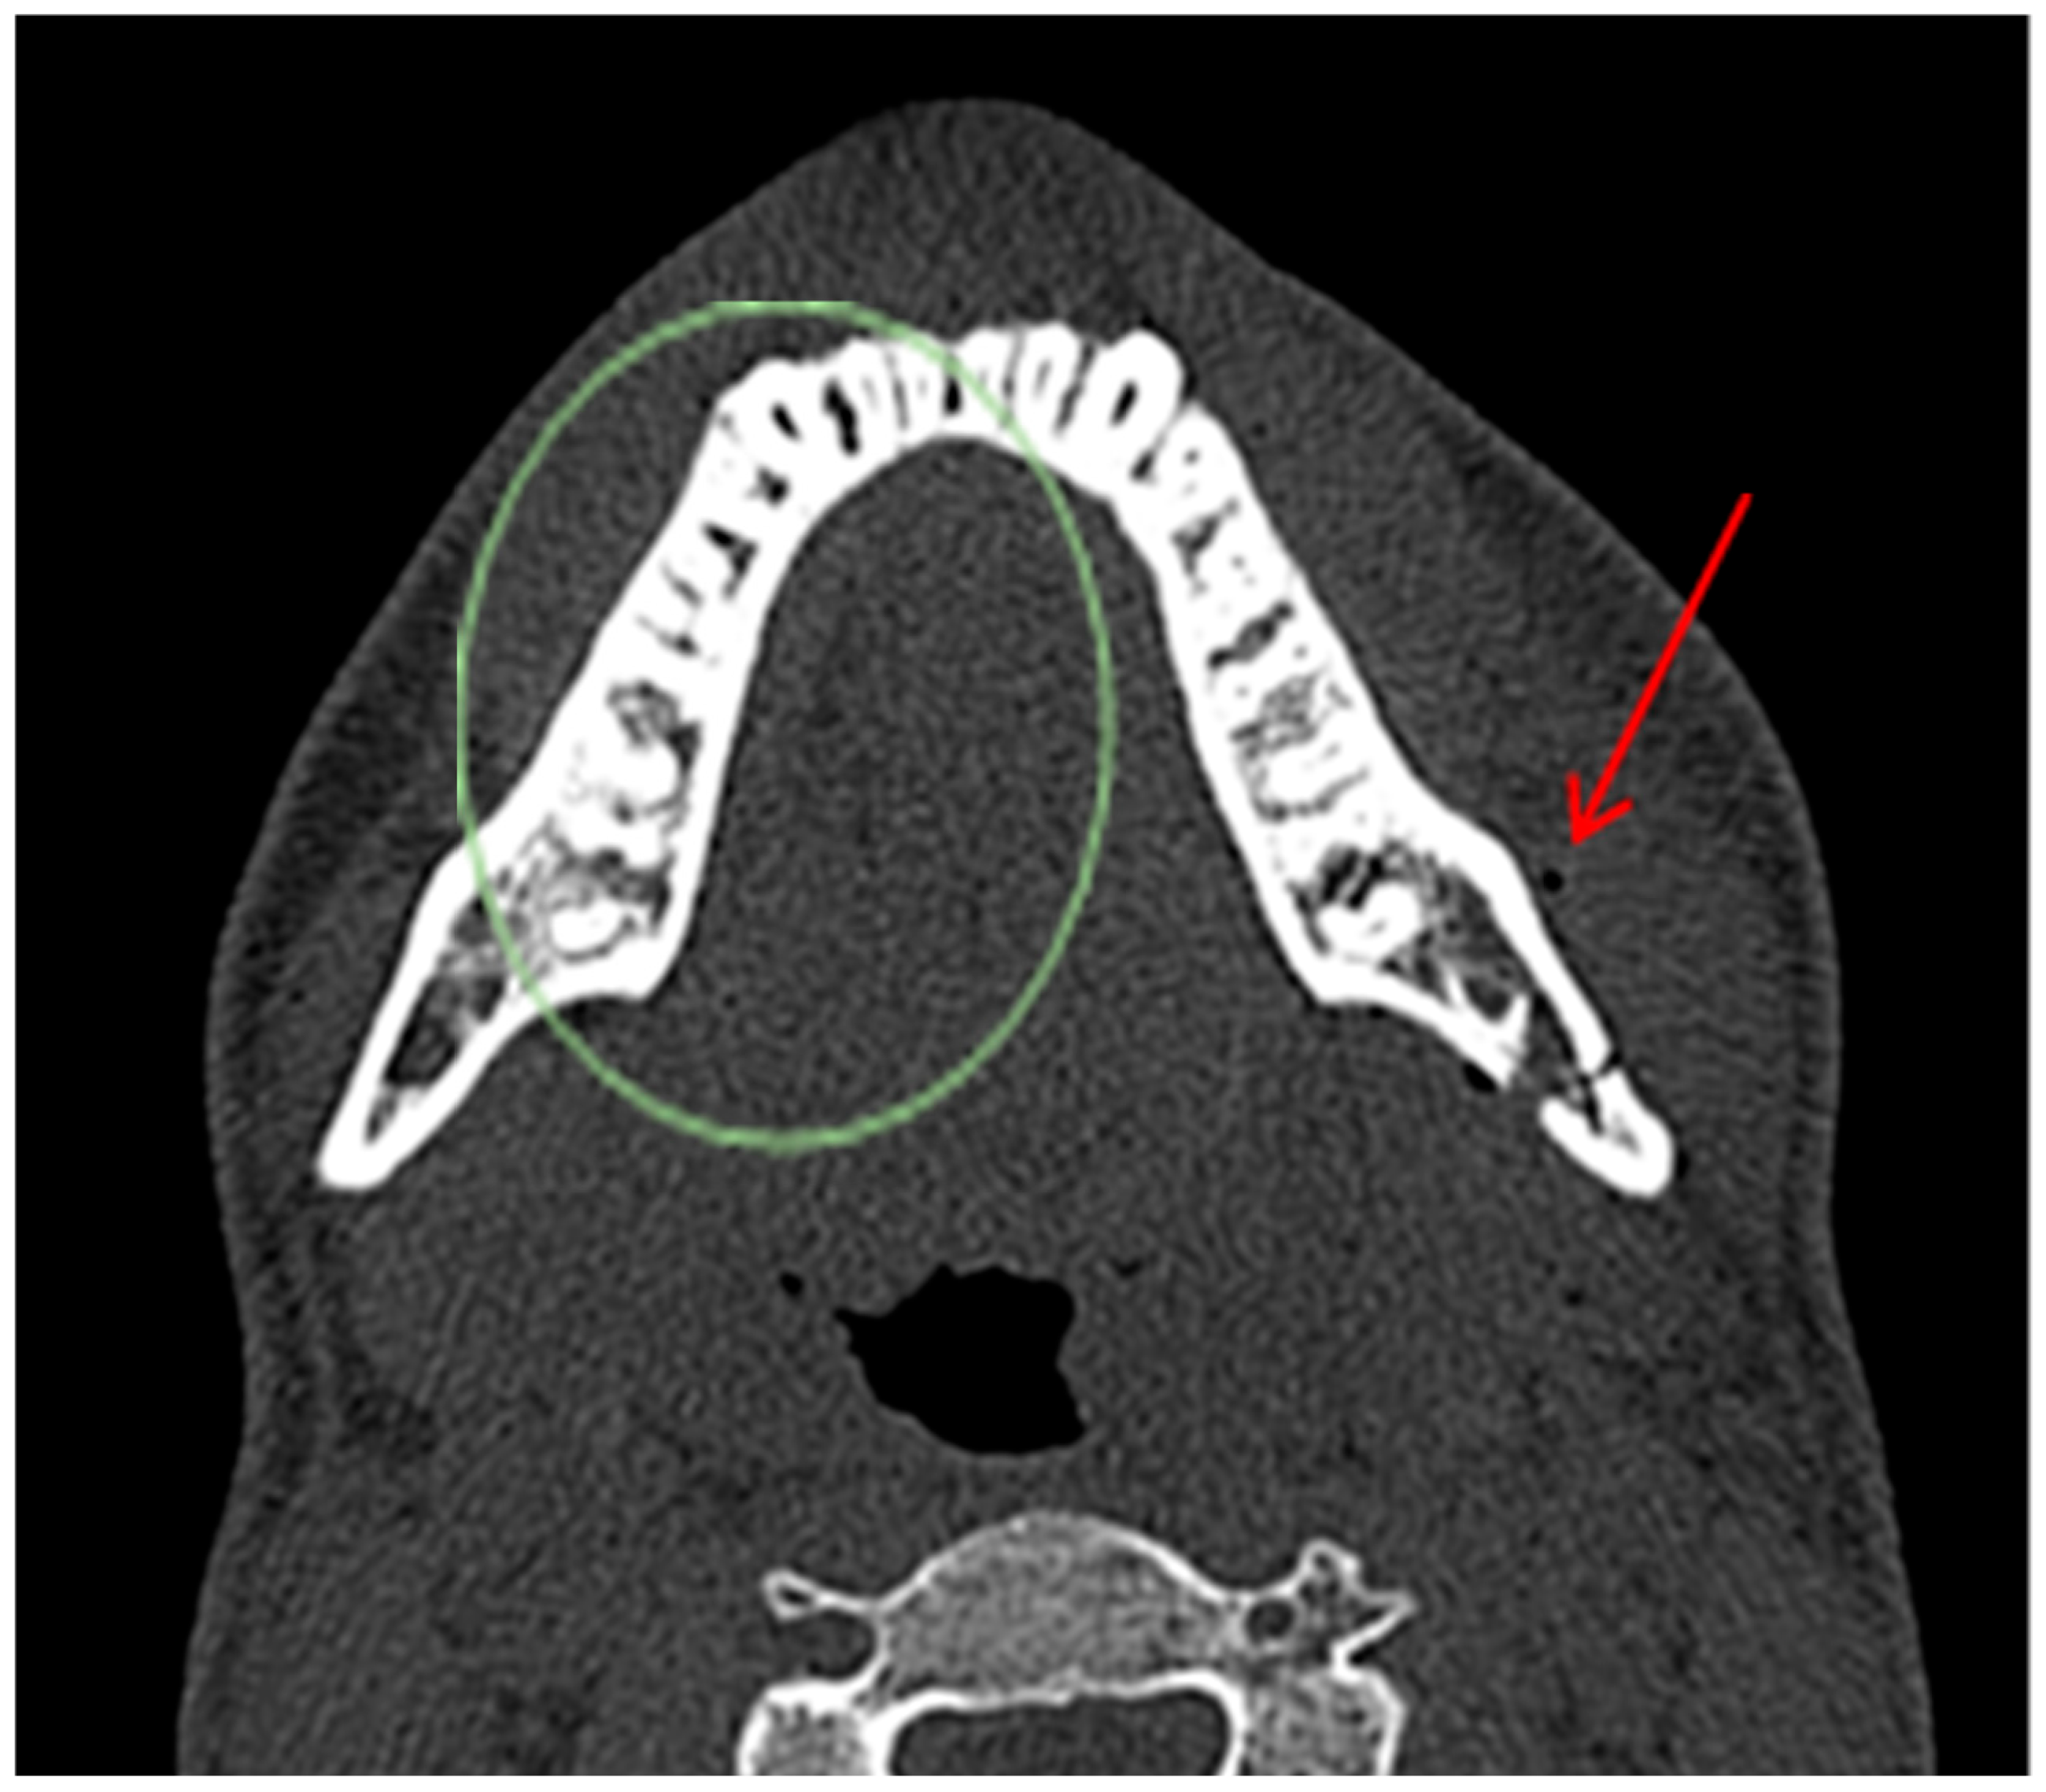

- Open fractures: located within the body/angle of mandible;

- Closed fractures: located within the ramus, condylar/coronoid process of mandible.

- True positive (TP)—diagnosed body/angle fracture + presence of AS in soft tissues.

- False negative (FN)—diagnosed body/angle fracture + no AS in soft tissues.